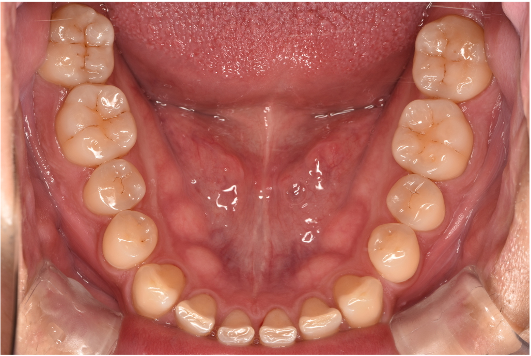

general 30代男性「タバコのヤニが気になる」縁上歯石・着色を除去し、その後歯周治療を行った症例

治療後

| 行ったご提案・治療内容 | 初診時はブラッシング方法などセルフケアについて説明を行い、縁上歯石・着色の除去を行いましました。 歯肉の炎症がある程度落ち着いたところで、後日再評価を行い歯周治療へ移行しました。 |

| 術後の経過・現在の様子 | 綺麗になったと喜んでいただき、この状態を保てるようセルフケアにも力を入れてくださっています。3ヶ月に一度の定期検診にも通っていただいています。 |